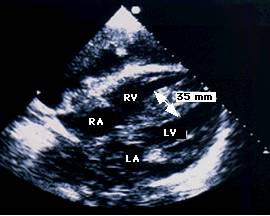

Ecocardiografia permite evaluarea afectarii functiei contractile, excluderea unor boli valvulare sau pericardice. Se apreciaza forma si functia VS (tipic VS globulos cu functie contractila global alterata), gradul insuficientelor valvulare, prezenta trombozei intracavitare (intraatriala sau intraventriculara). Cresterea dimensiunilor cavitatilor stangi si drepte este progresiva cu cresterea clasei functionale NYHA. Producerea emboliilor se asociaza cu dimensiunea VS si fractia de ejectie (FE).

Ecocardiografia si angiografia cu radionuclizi (ARN) evidentiaza dilatatia si hipokinezia sau diskinezia difuza a VD.

Ecocardiografia

Confirma diagnosticul de CMH, cuantifica elementele morfologice - distributia hipertrofiei, functionale - hipercontractilitatea VS si hemodinamice - gradientul intraventricular.